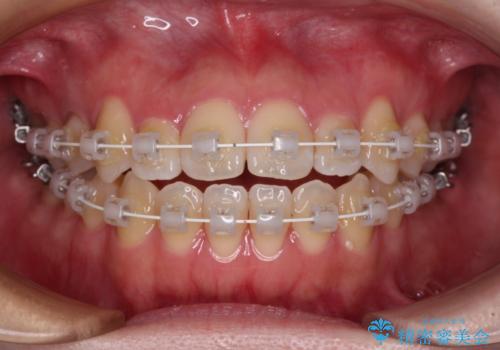

- 審美装置

- 1年6ヶ月

ワイヤー矯正での開咬改善には時間がかかります。

舌の突出癖改善のトレーニングをしっかりと行っていただき、上下前歯が接触する咬み合わせを達成することができました。